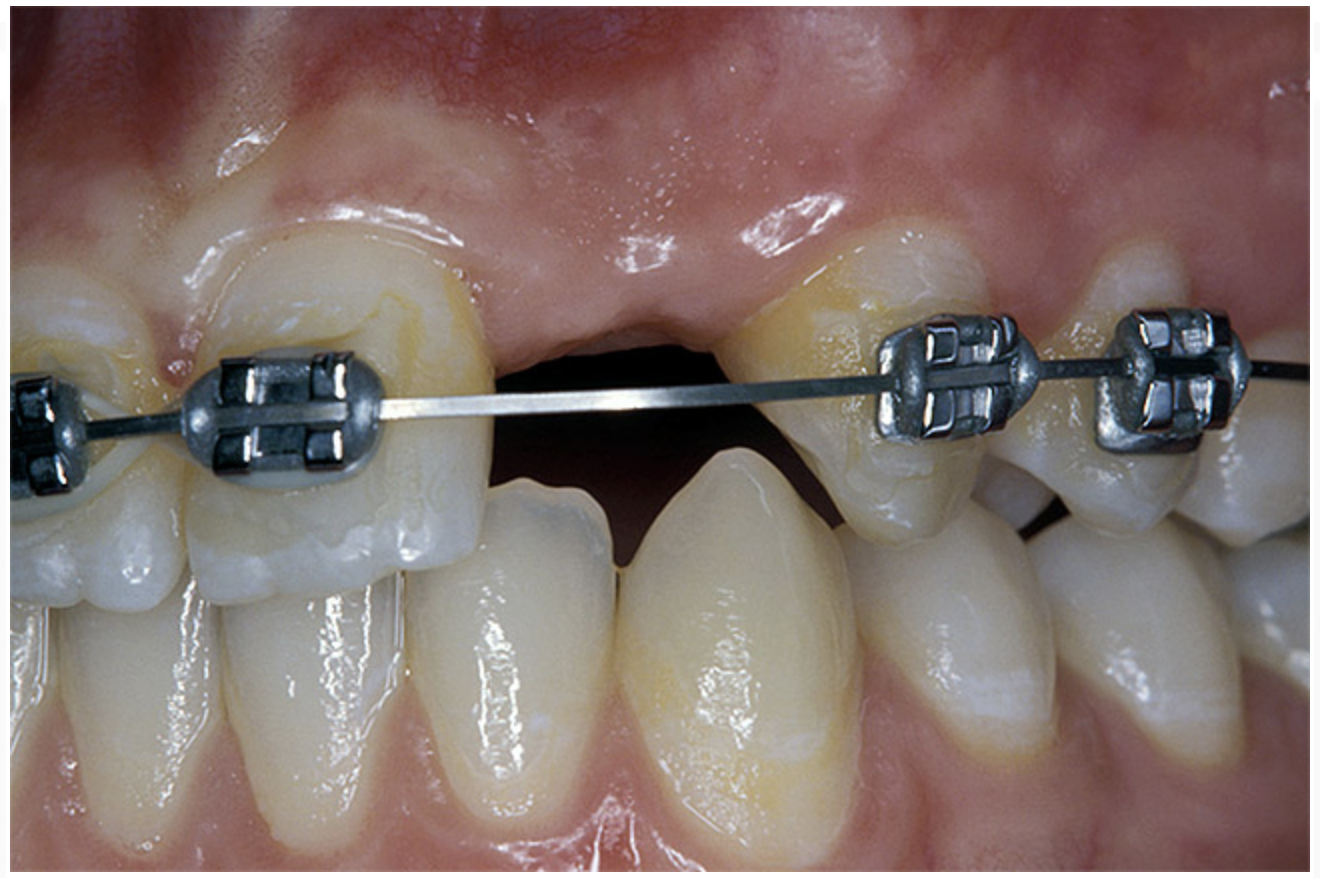

Periapical radiographs were taken to help determine the mesial-distal inclinations of the adjacent tooth roots (Figure 1). The radiographs revealed a serious issue, convergent roots for the right canine and right central, which eliminated that area as a potential implant-receptor site. The space between the left central and canine teeth was minimal, although the roots were relatively parallel. Clinical examination (manual palpation of the root eminences superiorly to the vestibule on the right side) confirmed the root convergence (Figure 2A). The flat, wide zone of the keratinized tissue and lack of interdental papilla was evident for the missing right lateral incisor. There was a marked difference in clinical appearance for the left lateral, which could impact the eventual plan of treatment (Figure 2B). Other significant clinical findings included bilateral facial bone concavities, which existed as a result of the congenitally missing tooth roots. As a diagnostic cue to the underlying bone topography, it is important to follow the demarcation between attached and unattached gingival tissue, and note the crestal width of the available keratinized tissue (Figure 2C).

Figure 2a  Pretreatment buccal views showed (A) root convergence, (B) a difference in clinical appearance of the left lateral, and (C) significant crestal width of keratinized tissue.

Figure 2b  Pretreatment buccal views showed (A) root convergence, (B) a difference in clinical appearance of the left lateral, and (C) significant crestal width of keratinized tissue.

Figure 2c  Pretreatment buccal views showed (A) root convergence, (B) a difference in clinical appearance of the left lateral, and (C) significant crestal width of keratinized tissue.